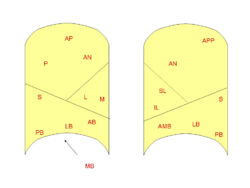

There are 10 bronchopulmonary segments in the right lung: three in the superior lobe, two in the middle lobe, and five in the inferior lobe. Some of the segments may fuse in the left lung to form usually 8-9 segments (4–5 in the upper lobe and 4–5 in the lower lobe).[1]

Right lung

- Superior lobe

- apical segment

- posterior segment

- anterior segment

- Middle lobe

- lateral segment

- medial segment

- Inferior lobe

- superior segment

- medial-basal segment

- anterior-basal segment

- lateral-basal segment

- posterior-basal segment

Left lung

- Superior lobe

- apico-posterior segment(merger of "apical" and "posterior")

- anterior segment

- Lingula of superior lobe

- inferior lingular segment

- superior lingular segment

- Inferior lobe

- superior segment

- anteromedial basal segment (merger of "anterior basal" and "medial basal")

- posterior basal segment

- lateral basal segment